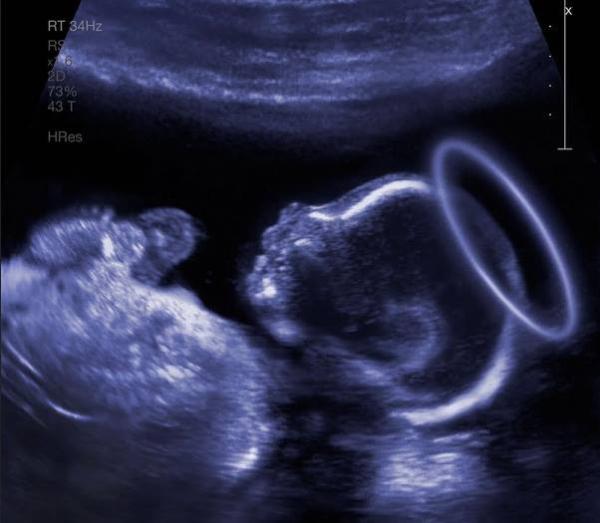

Ako prísť v ústrety Tebe, maličkému a bezbrannému, krehkému, ako už len novorodenec môže byť.

Pomôž nám byť tými, ktorí sa tešia z Tvojho príchodu ako rodičia, ktorým sa práve narodilo Dieťa. Daj nám nanovo pocítiť veľkú radosť z Tvojho narodenia. Krásneho chlapčeka Ježiška, nášho Pána.